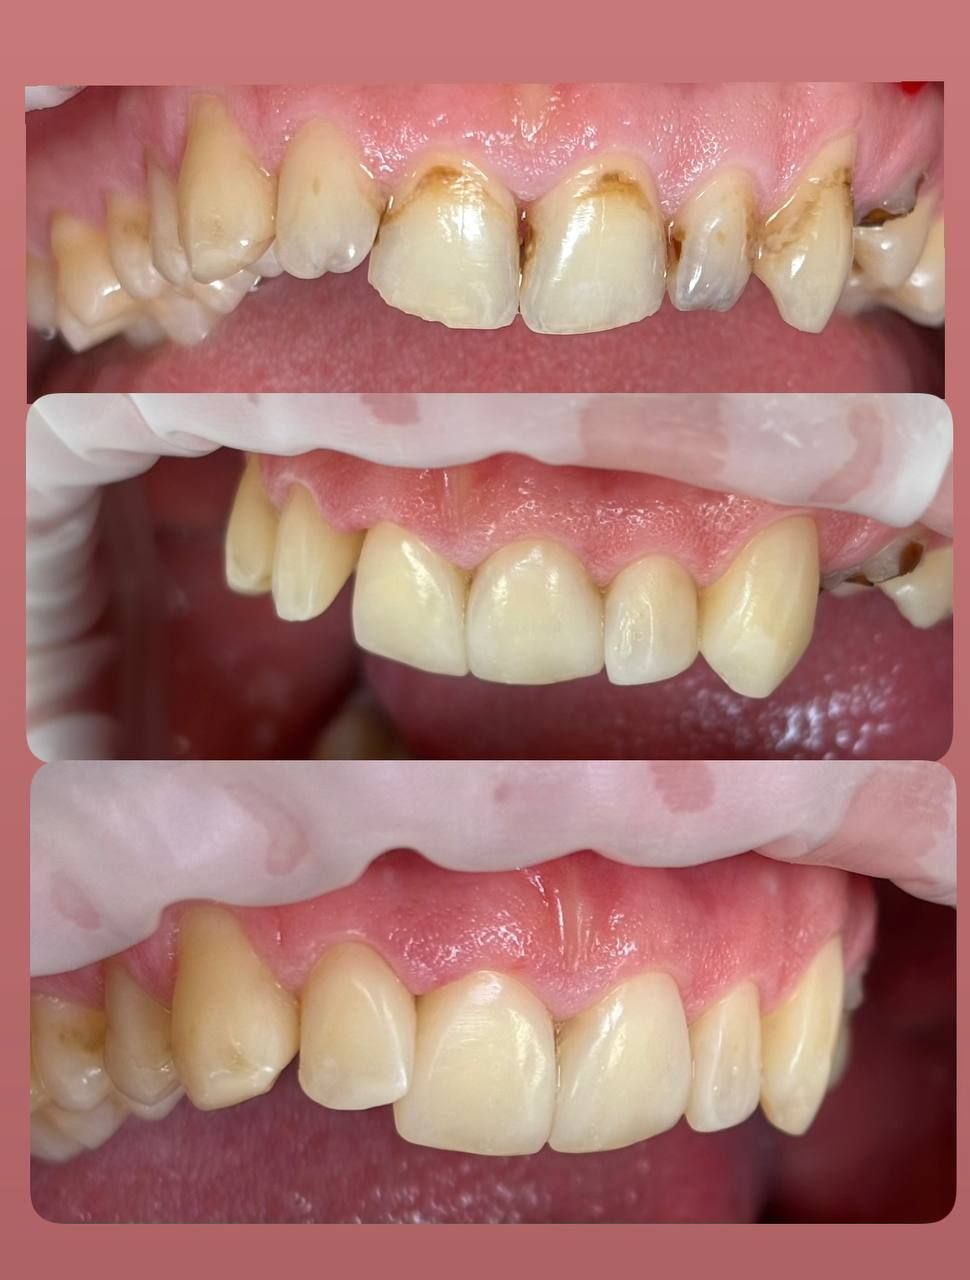

Jestem lekarzem dentystą zajmującym się stomatologią zachowawczą oraz leczeniem kanałowym pod mikroskopem (endodoncja mikroskopowa). W swojej pracy stawiam na kompleksowe podejście do zdrowia jamy ustnej – dokładną diagnostykę, skuteczne leczenie oraz profilaktykę.

Specjalizuję się w leczeniu próchnicy, odbudowie zębów oraz leczeniu kanałowym, w tym leczeniu kanałowym pod mikroskopem, które pozwala na bardzo precyzyjne oczyszczenie i opracowanie kanałów korzeniowych. Dzięki zastosowaniu mikroskopu możliwe jest skuteczne leczenie nawet bardziej skomplikowanych przypadków oraz powtórne leczenie kanałowe (reendo).

- Stomatologia estetyczna